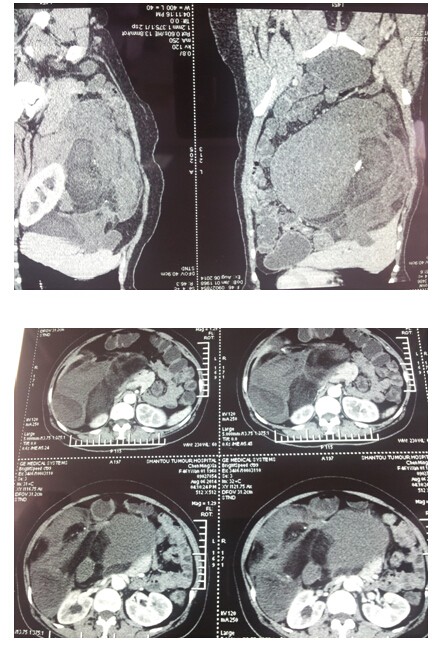

病例报告一例